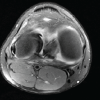

Both Mikulicz lines were slightly shifted medially on full-length frontal plain radiographs of the lower extremities. The % MA was 30.7% on the left side and 25.8% on the right side. Right and left femorotibial angles were 177° and 179°, respectively (Fig. 2). MRI showed incomplete DMM in both knees, with horizontal hyperintense areas on proton density-weighted fat-saturated images.

The lateral menisci of both knees had a complete DLM with a horizontal hyperintense area on proton density-weighted fat-saturated images in the left knee (Fig. 3).